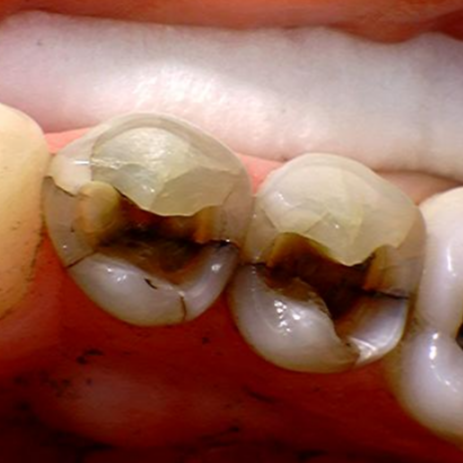

Usein varsinkin amalgaamilla paikatut hampaat ovat paikan alta halki jo pelkästään metallin ja lasimaisen hampaan erilaisten fysikaalisten ominaisuuksien takia. Siihen kun vielä lisätään vuosikymmenten pururasitus ja hampaan kulumisen aiheuttamien muodon ja voimien muutos, niin ei hampaiden halkeaminen kovinkaan suuri ihme ole.

Kuluneet, muotonsa menettäneet ja usein jo vuosikymmeniä rasitetut hampaat ovat lohkeamisalttiita sekä samoin jo vuosikymmeniä treenatut puremalihakset ovat erittäin vahvat. Tässä yhtälössä hampaat silloin tällöin joutuvat joustamaan halkeamalla heikoimmasta kohdastaan.

AMALGAAMILLA paikatut hampaat ovat paikan alta halki jo pelkästään metallin ja lasimaisen hampaan erilaisten fysikaalisten ominaisuuksien takia. Amalgaamia on käytetty hampaiden paikkauksessa lähes 200 vuotta.

On paljon hammasvaivoja, joihin on olemassa helppojakin hoitoja. Asiantuntevalta hammaslääkäriltä saat hammastarkastuksessa analyysin oman suusi terveydestä. Tässä kuvassa potilaan vaivana oli purressa lohkeavat hampaat. Kyseessä oli kuluneiden hampaiden väärään asentoon ohjaama (eli ristipurentaan) purenta ja sen myötä syntyneet lisävauriot, kulumat ja lohkeamat. Nämäkin hampaat hoidettiin kuntoon, suun terveys palautui ja ilmeestä tuli entistä ehompi, raikas ja hurmaava. Lue koko purentahoidon eteneminen tästä ja katso hämmästyttävät kuvat ennen ja jälkeen.

purentavirhe, ristipurenta